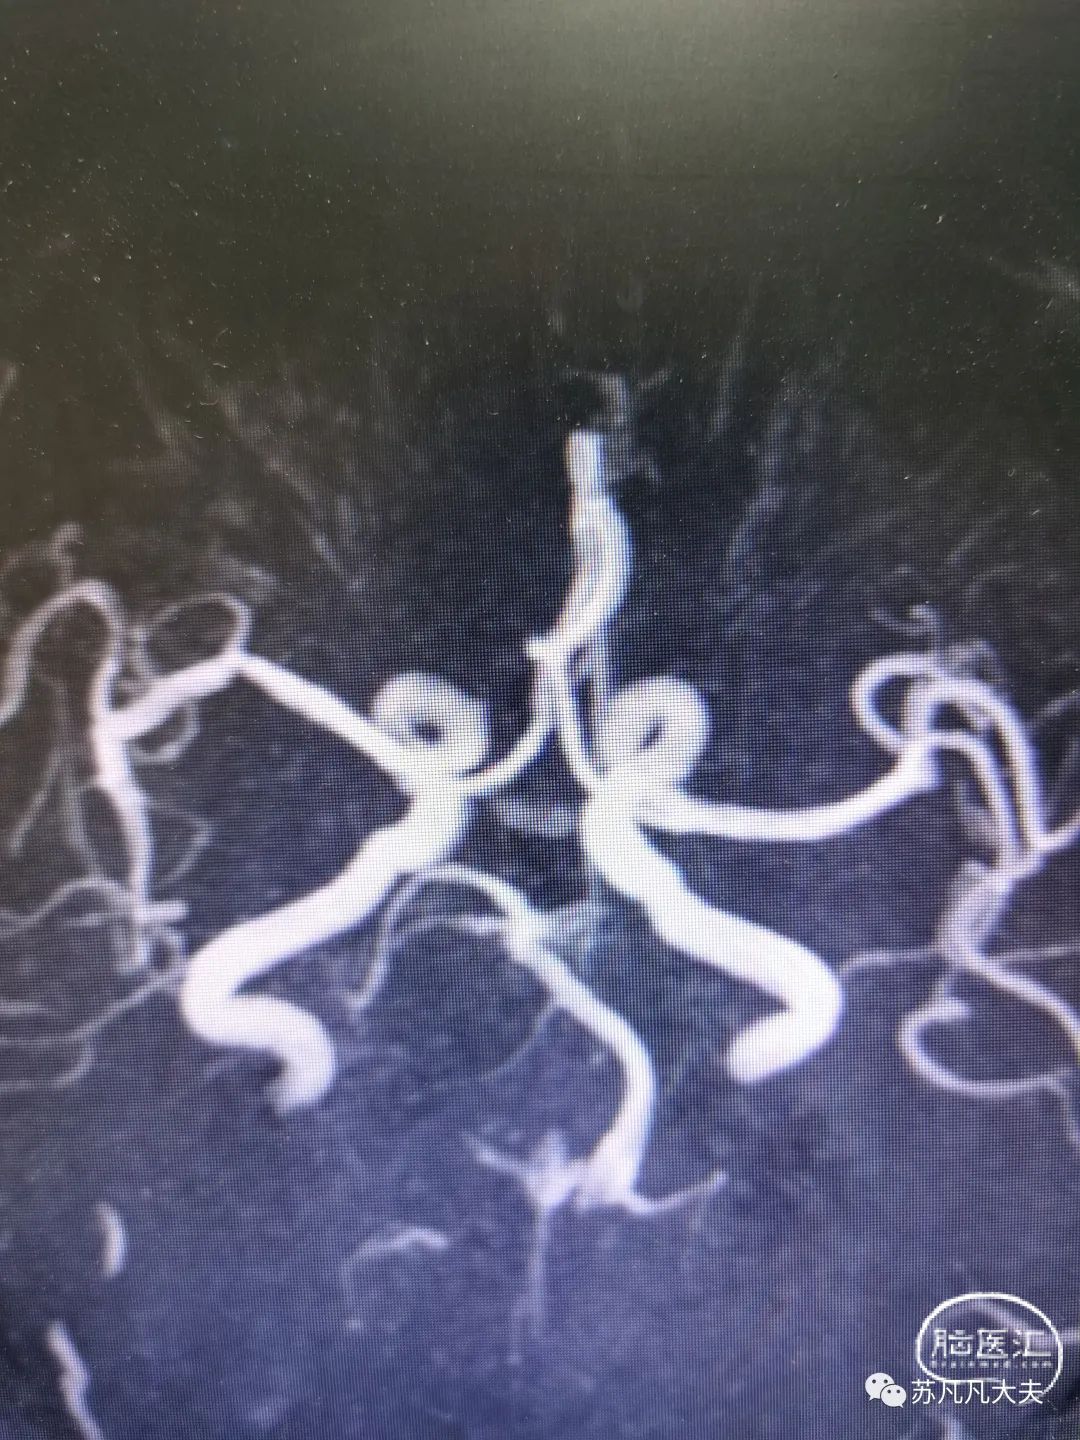

MRA示右侧椎动脉未显影,左侧大脑后动脉未显影。

DSA示右椎发育不良,颅内段闭塞

DSA示左椎优势,V4段极重度狭窄,左侧大脑后动脉未显影

脑血管造影提示

患者右椎发育不良,左椎优势,颅内段极重度狭窄,狭窄远端存在双侧小脑后下动脉,导致低灌注,同时左侧大脑后动脉未显影,考虑系狭窄基础上血栓形成后脱落致大脑后动脉栓塞。